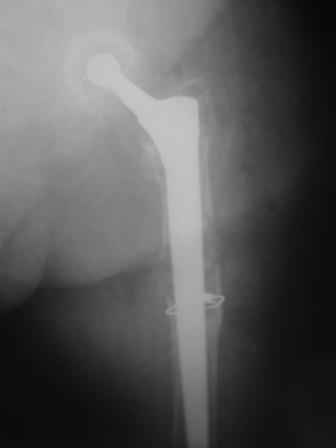

Спасибо за обсуждение. После нескольких дней тракции аппаратом сделали. Попытка закрытой репозиции не удалась из-за смещения по ширине, мешали фрагменты цемента. После их удаления репозиция получилась. Еще убрали немного цемента с ножки по латерльной стороне, чтобы обнажить 40-50 мм ее дистальной части, для плотной посадки гвоздя. Дальнейшее введение гвоздя было несложным. Протез показался нам стабильным в проксимальной части как латерально, так и медиально. Картинки в приложении.

THX for the discussion. After few days of traction by ex-fix the surgery was performed. An attempt of closed nailing was unsuccesful because of fragment translation, which was blocked by cement fragments. After removal of broken cement pieces reduction was reached "automagically". Also some cement from lateral part was removed by

chisel to expose distal 40-50 mm of the stem to allow tight fit of the nail. Further fixation by the nail was pretty easy and straightforward. Images attached. The stem looked stable in its proximal part both laterally and medially. Comments/critics are welcome.

Комментарии и критика приветствуются.